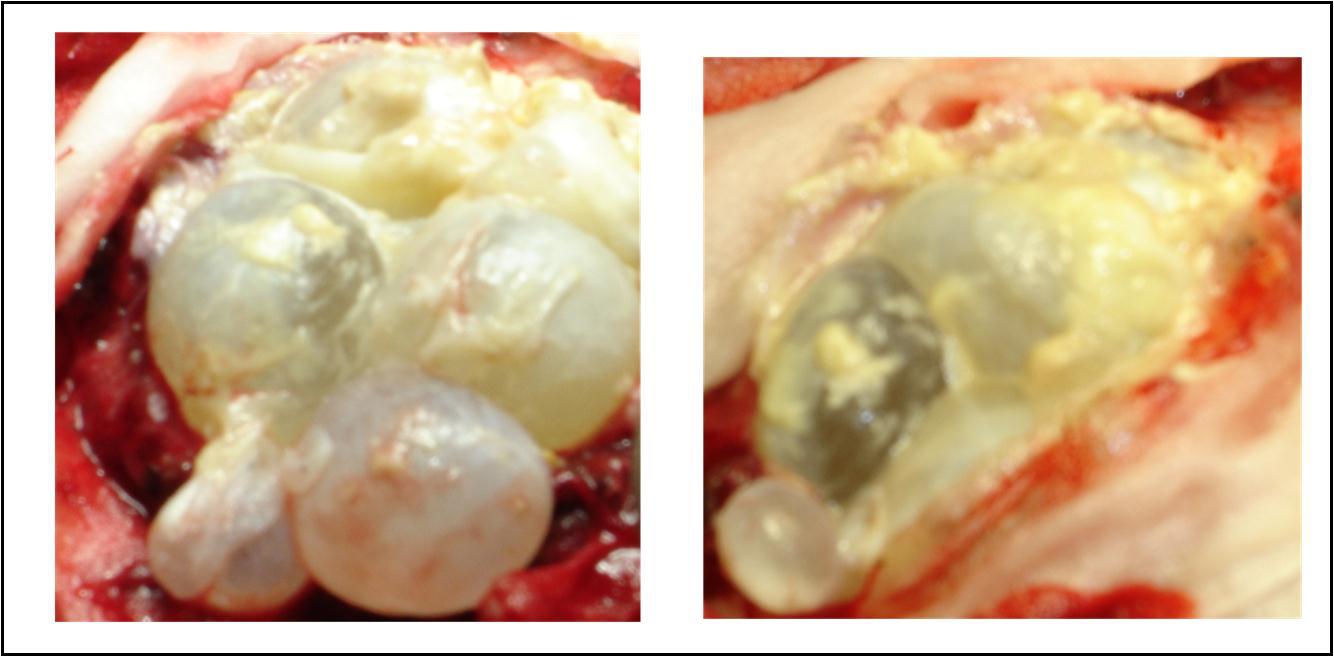

A 27 years-old male patient was admitted with 1 month history of headache, fever, short term memory lack, aphasia, right hemiparesis and seizures. He had liver hydatid cysts excised 8 years before and was treated with adjuvant medication (albendazole). The neurological examination revealed right central third cranial nerve palsy and hemi paresis, with Babinski sign positive, aphasia and papilledema on ocular fundus. The Glasgow Coma Scale was evaluated to 10/15 (E:3; V:1; M:6). A brain CT scan showed a large left temporoparietal intracerebral multiple and calcified hydatid cysts, important mass effect with midline shift about 7 mm following by an obstructive hydrocephalus (Figure 1). Other cysts were found in thalamic region (Figure 2). The Thoraco-abdominal CT scan showed multiple intra peritoneal hydatid cysts (Figure 3). A left temporo parietal craniotomy was performed in emergency. After corticectomy, using Arana-Iniguez technique, the appearance of the capsule suggested infected hydatid cysts with a purulent material which was aspirated. Numerous hydatid cysts were lifted away and several daughter vesicles were carefully removed without rupture (Figure 4). Macroscopically, the abscess wall appeared to be thick, calcified and tightly attached to lateral ventricular, so it could not be removed. The deep cyst overlying the third ventricle was left.in place. Microscopic examination demonstrated live scoleces, protoscoleces and multiple hooks. These findings are consistent with hydatid cyst (granulosis ecchinococcus) (Figure 5). Bacteriology examination found several white blood cells in the pus (neutrophilia) and infection by streptococcus pneumonia. This was consistent with infection. After surgery, the patient had medication (albendazole, specific antibiotherapy and phenobarbital). The inflammation assessment in the blood showed leukocytosis, a high C-reactive protein rate and increased erythrocyte sedimentation rate. Post operative CT scan was performed and showed the residual calcified capsule and decreased ventricular size (Figure 6). Clinical improvement was achieved after treatment. One month after the initial diagnosis, CT scan of the brain showed no recurrence and a physical examination revealed a neurologically intact, fully functional patient and eyes fundus normal. He was discharged and went to abdominal surgery two months later with complete intra abdominal cysts removal. Albendazole treatment was continuing for six months and radiological exploration was performed by brain MRI with spectroscopy at three and six month later. This showed that infection had resolved and the deep cyst overlying the third ventricle is less spherical (Figure 7, Figure 8). Four years later, the outcome was good.

Figure 4.per operative view showing multiple hydatid cysts with purulent material